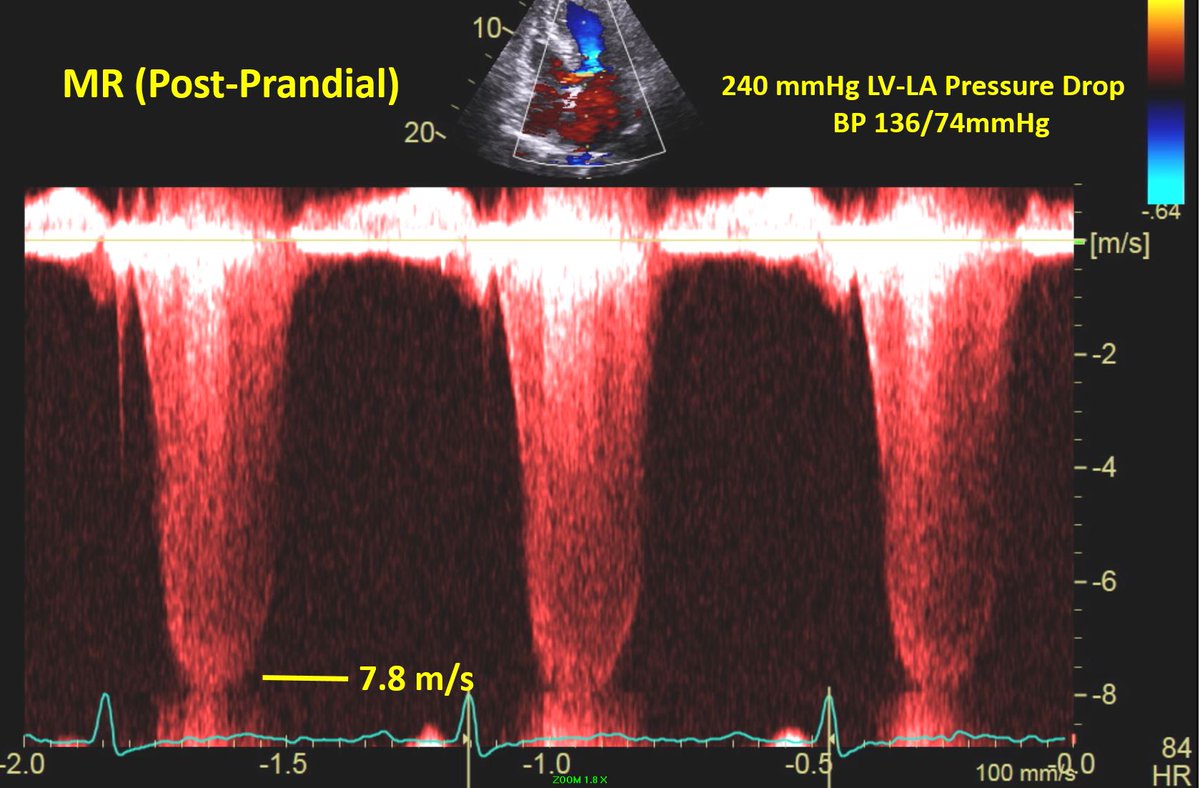

Recent case of a middle aged pt with HCM Echo performed late morning demonstrated no LVOT obstruction (fasting). Patient returned for consultation following lunch & was noted to have loud, harsh 4/6 SEM. Doppler study was repeated which demonstrated severe LVOT obstruction!

Patient concurrently developed severe MR with high velocity jet. This case illustrates the severe hemodynamic effects of eating in some HCM patients with dynamic LVOT obstruction.